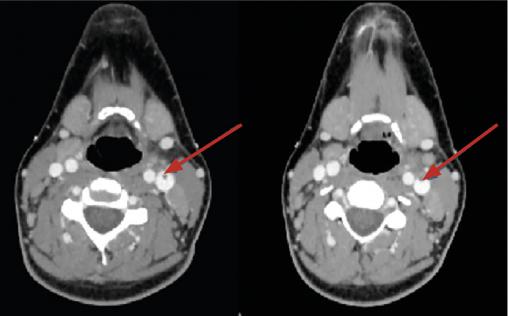

Le scanner cervico-thoracique (fig. 1 et 2 ) montre une thrombose de la veine jugulaire interne gauche ainsi qu’un épanchement pleural bilatéral et une pneumopathie des deux côtés sur emboles septiques, permettant de poser le diagnostic de syndrome de Lemierre.

Le scanner cervico-thoracique (